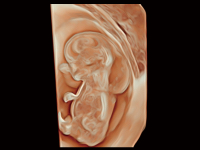

作为开立医疗全新打造的超高端旗舰超声产品,从探头抬起唤醒开启扫查到多维探头发射接收,通过先进的场成像发射、自适应聚合重建等技术,基于RF Data原始射频数据在图像生成、高端功能等方面实现突破,为妇产科、儿科提供全方位临床解决方案。

梦溪®P80以“关爱女性”为基石,提供全方位的解决方案,量身定制以满足女性的健康需求,涵盖妇科、生殖健康检查、产前筛查及产后康复等领域。